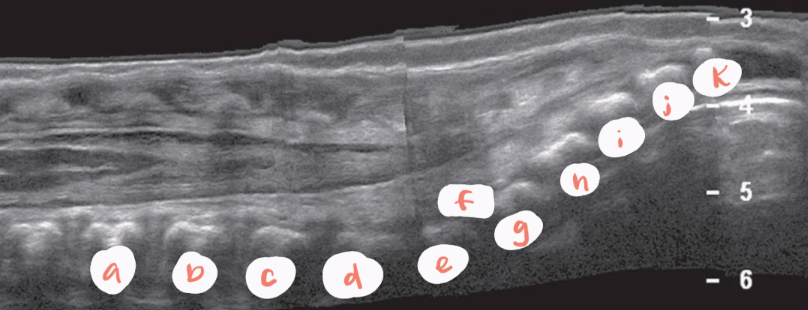

a

L1

b

L2

c

L3

d

L4

e

L5

f

S1

g

S2

h

S3

i

S4

J

S5

arrow

filum terminale

red arrow